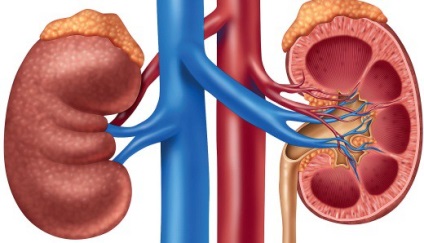

In mod normal, rinichiul se află în patul renal, care este îndreptată spre mănunchiul neurovasculare. În ligamentele dețin corp cutie, fasciei, presiunea din interiorul abdomenului, fascia renală și țesutul adipos perirenal.

deplasarea rinichi are loc la 8-a săptămână de embriogenezei. Inițial, rinichiul este în cele din urmă pelviana a fructelor, dar apoi migreaza spre regiunea lombară.

Simultan cu ascensiunea este rotit din poziția mănunchiului vascular interior, apoi în față, și apoi spre exterior.